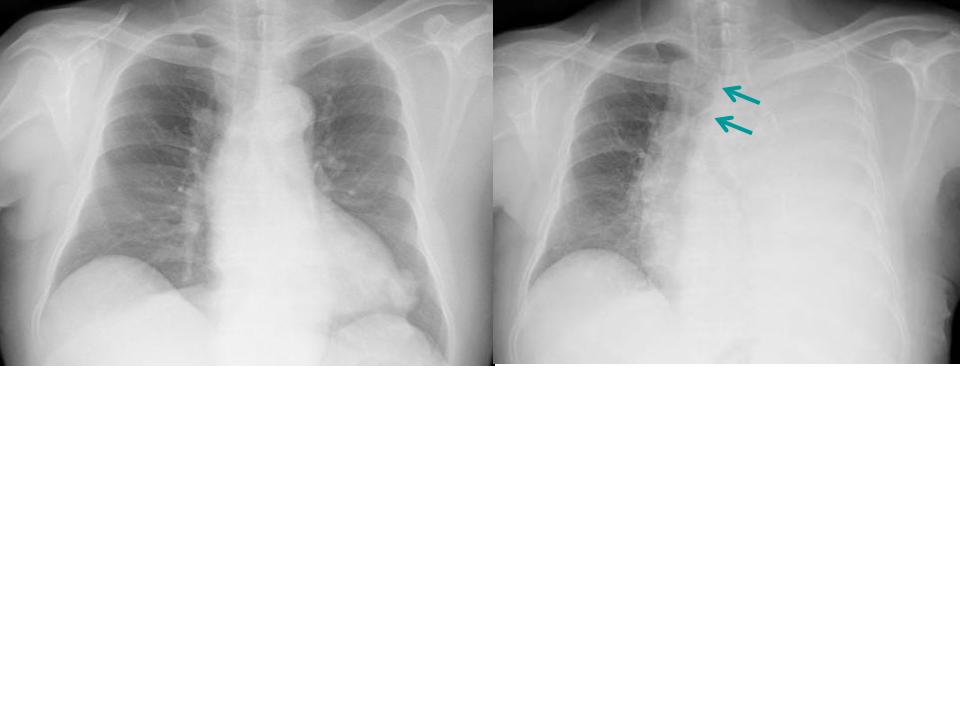

B正面像で見えるリンパ節

傍気管線、A-P window、気管分岐部は必ずチェックしましょう。

C縦隔や横隔膜の動きを見る

これらの動きから、肺容量の増減がわかります。